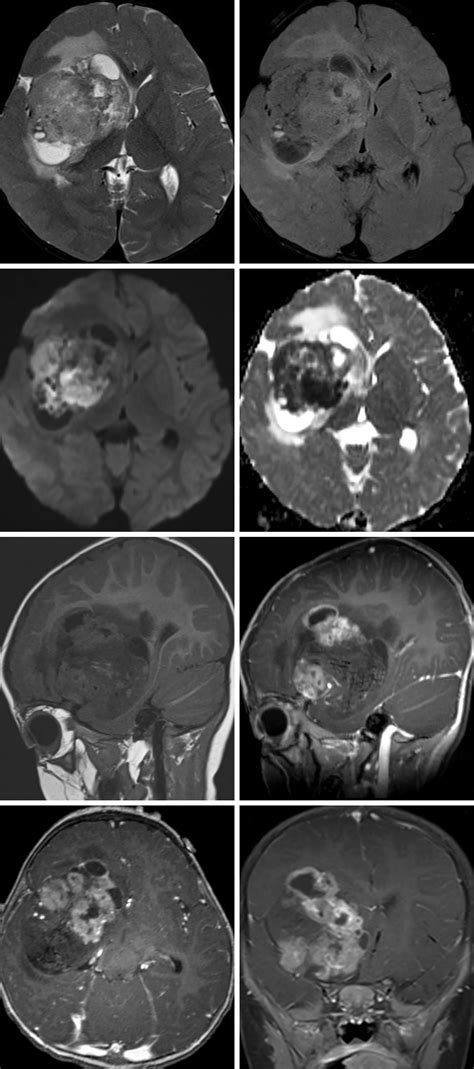

Diagnosis typically begins with advanced neuroimaging, such as MRI scans with and without contrast, to visualize the tumor's size and location. However, imaging alone is rarely sufficient. A definitive diagnosis is achieved through a surgical biopsy or total resection, followed by a rigorous pathological examination. Pathologists look for the loss of INI1 protein expression in the tumor cells, which serves as a molecular hallmark for an Atypical Teratoid Tumor.

• Atypical Teratoid Rhabdoid Tumor MRI